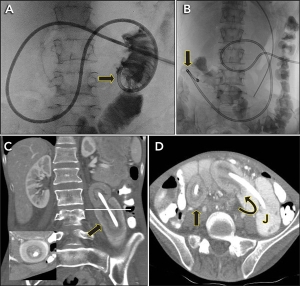

A 27-year-old woman was being treated with gastrojejunostomy feeding for severe anorexia nervosa. The position of the gastrojejunostomy tube was checked by fluoroscopy on the day of insertion (Figure, A, arrow). The next day, the patient presented with abdominal pain and “shortening” of the external portion of the tube. Repeat fluoroscopy showed migration of the tube (Figure, B, arrow). Computed tomography showed two segments of jejunojejunal intussusception (Figure, C, arrow and inset, and D, straight arrow) centred around the tube (Figure, D, curved arrow), with an intervening segment of normal jejunum (Figure, D, label J). The patient’s gastrointestinal tract was intact. The intussusceptions were reduced by applying traction on the tube under fluoroscopic guidance, and the patient resumed tube feeding without recurrence.